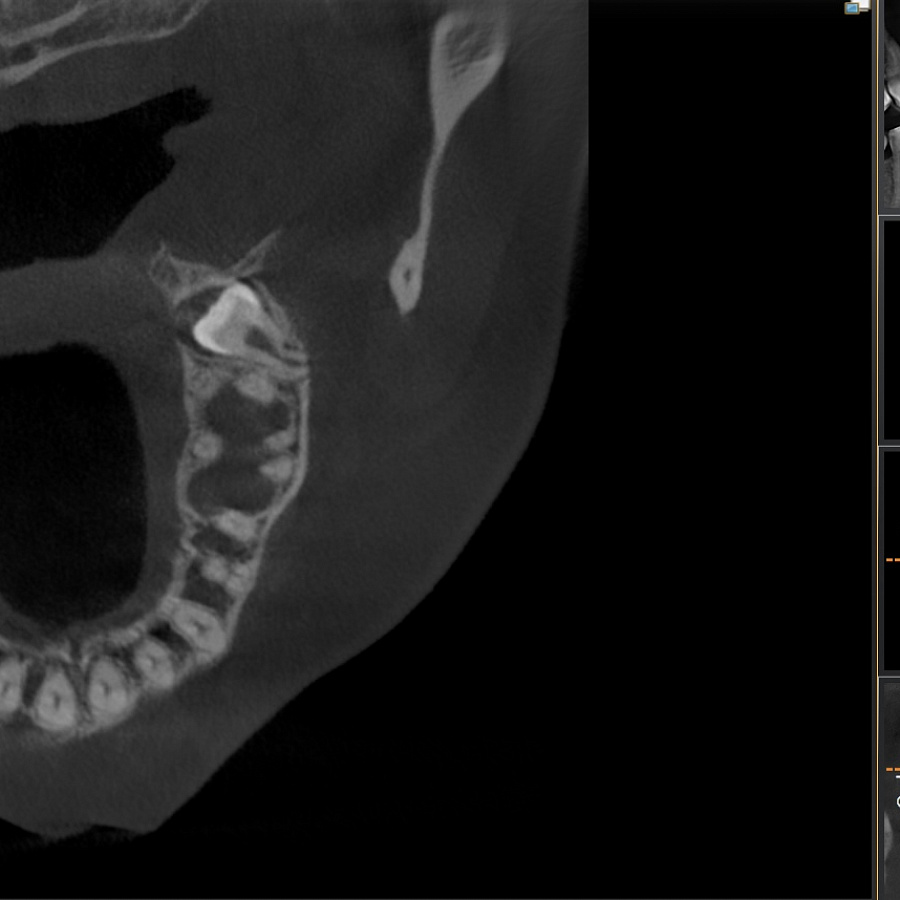

Зуб не прорезался, лежит горизонтально и направлен в сторону твёрдого нёба, мешает проведению ортодонтического лечения, выпрямлению зубных рядов. Около зуба проходит несколько важных анатомических структур, которые нельзя задеть, плюс зуб полностью погружён в костную ткань.